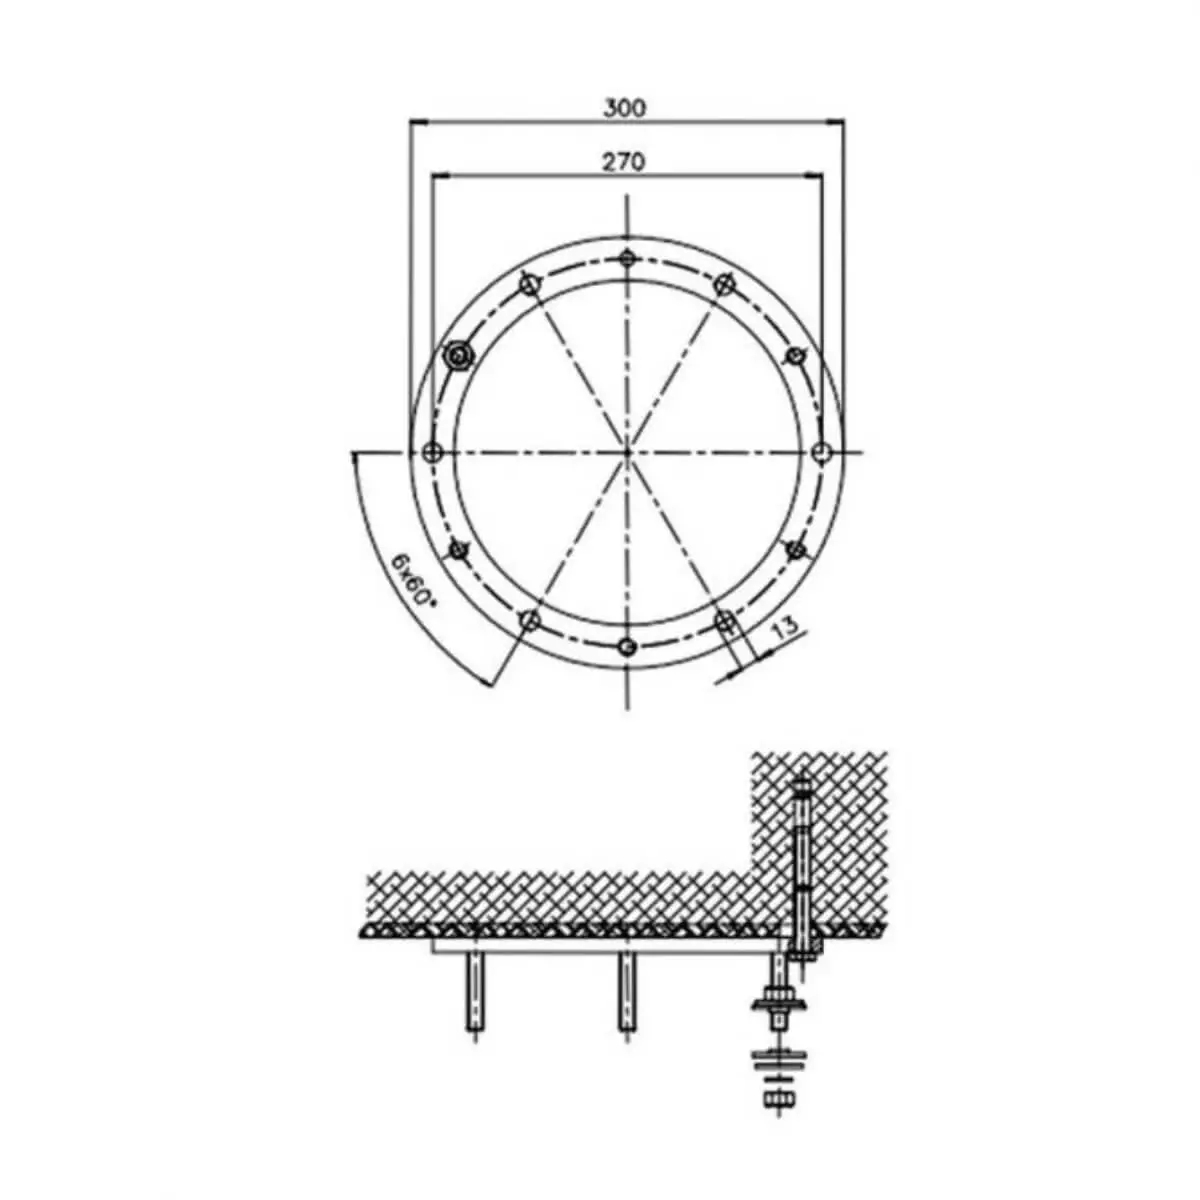

- Sonde convexe C361-2

- Applications : abdomen, obstétrique, urologie

- Fréquences : 2,5 MHz ; 3,5 MHz ; 4,5 MHz ; H5,0 MHz ; H5,4 MHz